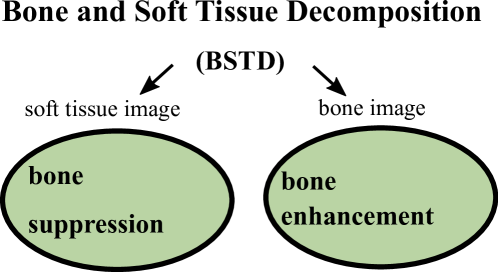

These limitations motivate us to develop a new and generic mathematical model. Instead of suppressing bones or soft tissue, our model decompose one X-ray image into one soft tissue image and one bone image. These two images have exactly the same imaging domain. Our task is fundamentally different from bone enhancement task and bone suppression task. In fact, our method simultaneously does bone enhancement and bone suppression. As illustrated in Fig. 3, our soft image can be considered as bone suppression while our bone image can be considered as bone enhancement.

Different from the bone enhancement or suppression, we propose to decompose the input X-ray image into one bone image and one soft tissue image. Such task is named as Bone and Soft Tissue Decomposition (BSTD). We construct a new mathematical model that can effectively decompose the soft tissues in X-ray images. Our method decomposes the input X-ray image into background image (soft tissue) and bone image. Be aware the difference between our model and the bone segmentation task. Bone segmentation separates the imaging domain into bone region and background region (without overlap). However, our background and bone images share the same imaging domain (exactly overlapped with the same imaging domain). Such difference is illustrated in Fig. 4.

II Our Method